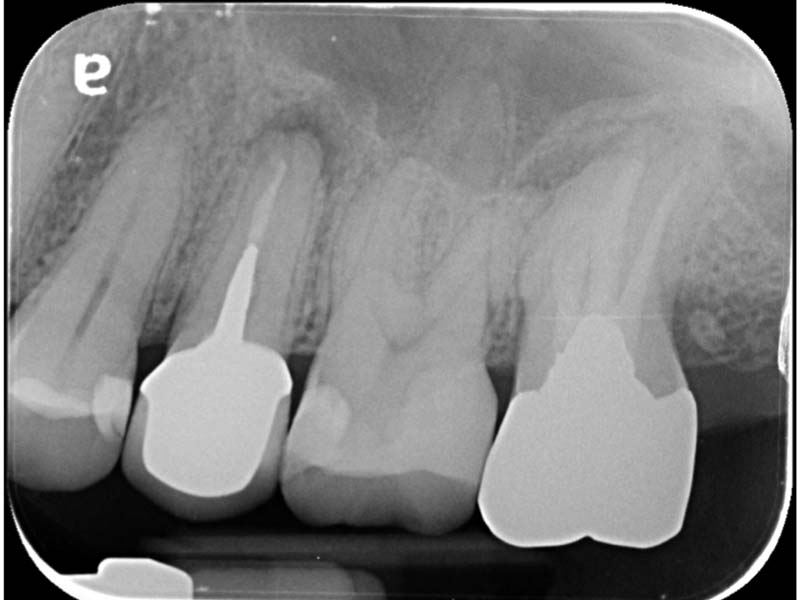

治療前X光:診斷左上顎最後三尺為均需要根管治療

左上顎第二小臼齒:顯微鏡下確診牙裂,建議拔除

左上顎第一大臼齒:為五根管的難症(罕見變異多根根管)

左上顎第二大臼齒:也是五根管的難症(罕見變異多根根管)

治療後X光